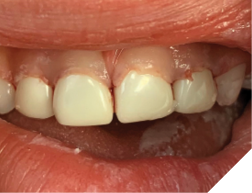

One treatment modality that is effective with incipient decay of this nature is professionally applied Silver Diamine Fluoride (SDF). SDF can help to arrest or slow down the progression of the lesions. One side effect that parents need to be warned about is black staining. It is important to discuss this before the treatment because it may introduce a real esthetic concern. If the teeth are extensively decayed, and with draining fistulas, the only treatment may be extraction of effected teeth (Fig. 3). If the teeth have cavitated lesions, then restorative options can be given. This usually involves an extensive treatment plan with sedation, typically a general anaesthetic (GA). For the very young, treatment should only be caried out at a hospital for safety reasons. Restoring the teeth will give the child a full functioning dentition and let the jaws develop properly. The ideal restoration for gross decay from ECC is a full coverage crown. The best being zirconium crowns (Fig. 4) or stainless steel with plastic white facings. Since the work is done under GA, the best and strongest treatment options should be considered. This will help to prevent further treatments due to failure that could involve subsequent sedations.

Fig. 3

Fig. 4